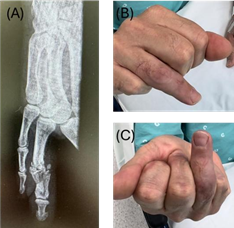

55-year-old male, factory worker within the footwear industry with 35 years of activity. He suffered a work accident in May 2024 which resulted in an exposed fracture of the middle and proximal phalanges of the right ring finger by high energy crushing in a pressing machine (Figure 1).

Figure 1: X-Ray of the exposed fracture of the middle and proximal phalanges of the right ring finger.